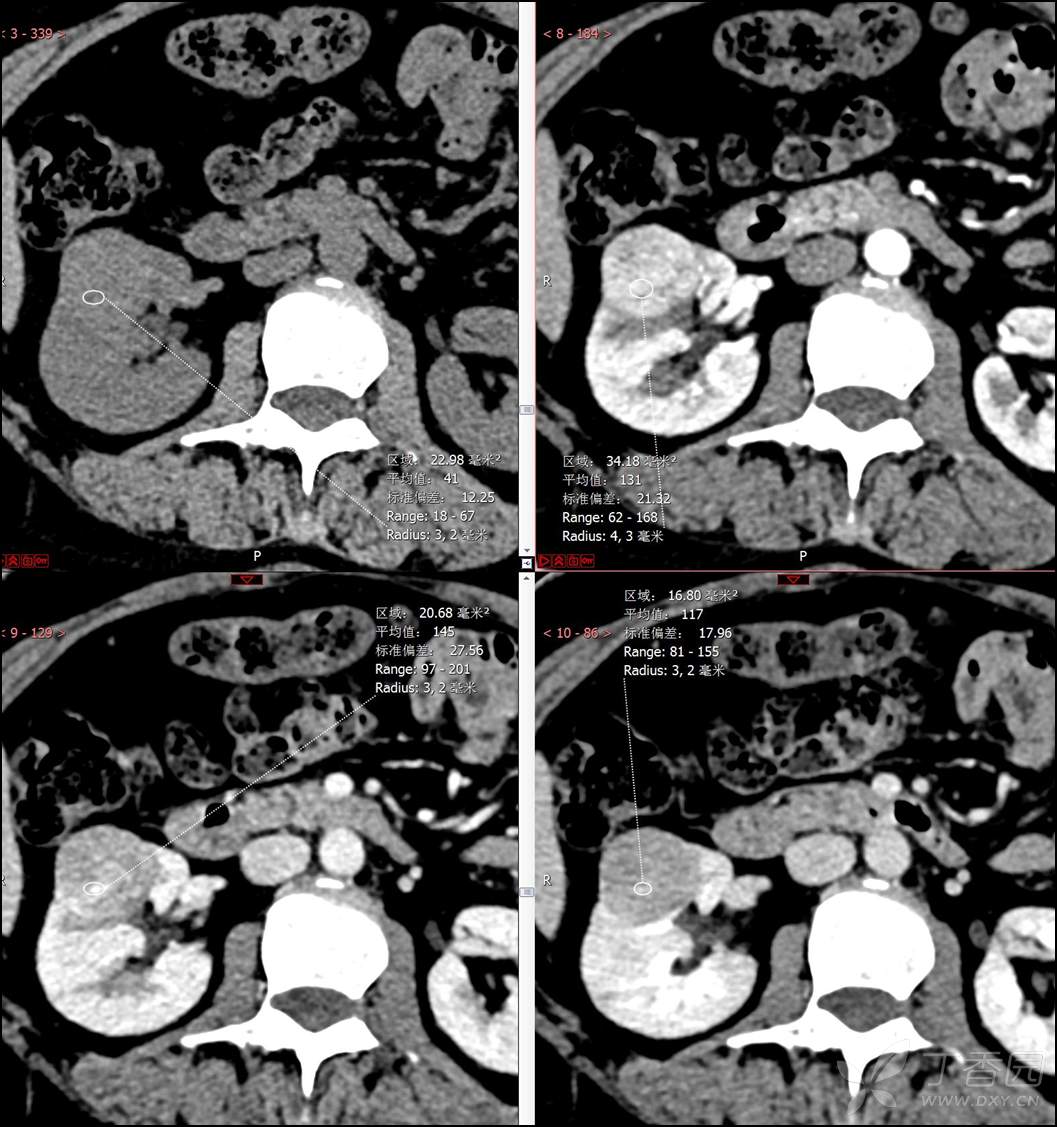

【影诊笔记516】中年女性,检查发现肾占位2周就诊~『嗜酸细胞腺瘤』

主诉:检查发现肾占位2周

简要病史:患者2周前体检发现肾实质性占位,无腰痛,无血尿,无尿频、尿急、尿痛,无发热,在外未行特殊治疗。患者为行进一步治疗就诊于我院,门诊以“肾占位性病变 ”收入我科,患者自发病以来,神志清,精神可,小便如上所述,大便正常,体重无显著变化。